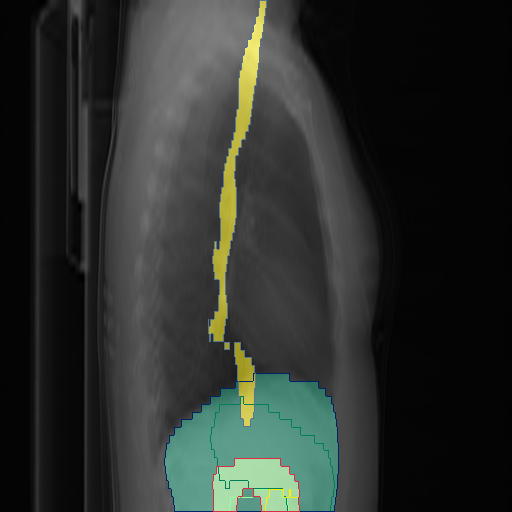

We show qualitative results for frontal projections in Fig. 2. We show a subset of classes belonging to the supercategories lungs, vascular systems, bones, and abdomen/digestive system. The predictions show minor deviations at the boundaries of the individual classes of the respiratory and vasculature system, while some inaccuracies become visible in the abdominal area. The qualitative results for the lateral projections are displayed in Fig. 2. Akin to the frontal view, the predictions show smoother borders but align with the ground truth. Apart from this, the segmentations provide matching insights on the thoracic anatomy with a slight deviation from the ground truth for both frontal and lateral views.

We display qualitative results in Fig. 3. The annotators tend to be content with most annotations. There are edits at the extensions of the esophagus, trachea, and aorta and corrections of the lower ribs. There is little consensus for classes in the abdominal area, such as the stomach, as seen on the right of Fig. 3 . In contrast, the annotators often align for bone classes.